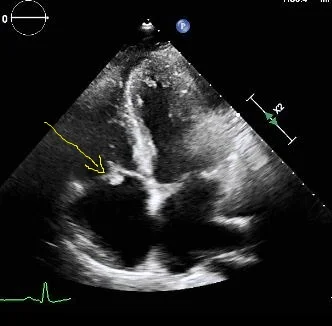

Careful analysis shows a small filling defect adjacent to the tricuspid valve, and a dilated right atrium. Tricuspid endocarditis confirmed on echocardiography.

Image from transthoracic echocardiogram confirms vegetation on tricuspid valve (yellow arrow)